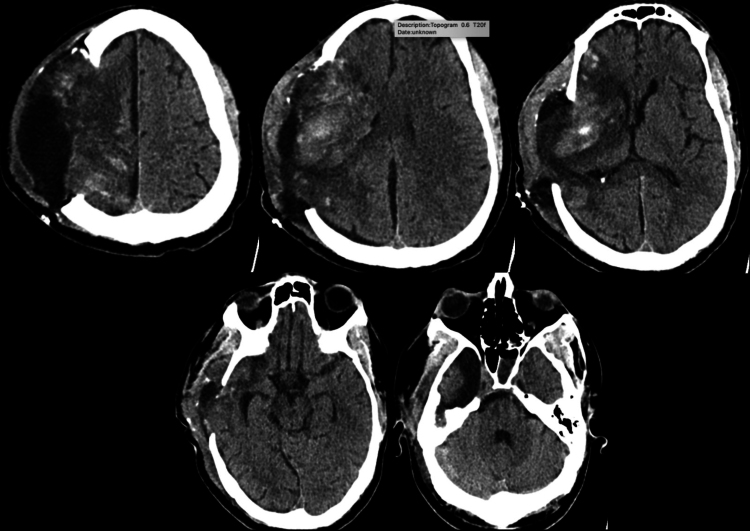

背景:恶性大脑中动脉(MCA)梗死导致脑水肿,可导致脑疝和死亡。标准治疗包括减压性半颅切除术(DHC)和综合神经危重症护理。尽管采取了这些措施,一些患者的病情仍会继续下降。重新开放头皮切口可能允许额外的减压,并提供死亡率的好处。观察:一名47岁男性在静脉溶栓和不成功的机械取栓后发生恶性右MCA区域梗死。尽管积极的高渗治疗和大DHC,患者继续表现出临床衰退和脑水肿的影像学进展。因此,重新打开头皮切口以促进最大程度的脑外疝,作者认为这是治疗脑肿胀的关键策略。在此期间,考虑到暴露的脑表面和潜在的脑脊液泄漏相关的感染风险增加,患者继续使用预防性抗生素。脑肿胀消退后,行右半球部分切除术切除梗死半球。值得注意的是,在干预和延长的康复期后,患者取得了显著的功能恢复。经验教训:本病例突出了恶性脑梗死手术治疗中遇到的复杂性,特别是当标准减压措施失败时。https://thejns.org/doi/10.3171/CASE2523。

Observations: A 47-year-old man developed malignant right MCA territory infarction following intravenous thrombolysis and unsuccessful mechanical thrombectomy. Despite aggressive hyperosmolar therapy and a large DHC, the patient continued to exhibit clinical decline and radiological progression of cerebral edema. In response, the scalp incision was reopened to facilitate maximal external cerebral herniation, a strategy the authors believe was critical in managing the brain swelling. The patient was maintained on prophylactic antibiotics during this period, given the increased infection risk associated with exposed brain surface and potential CSF leakage. Following the resolution of cerebral swelling, a right partial hemispherectomy was performed to excise the infarcted hemisphere. Notably, the patient achieved significant functional recovery following the intervention and an extended period of rehabilitation.